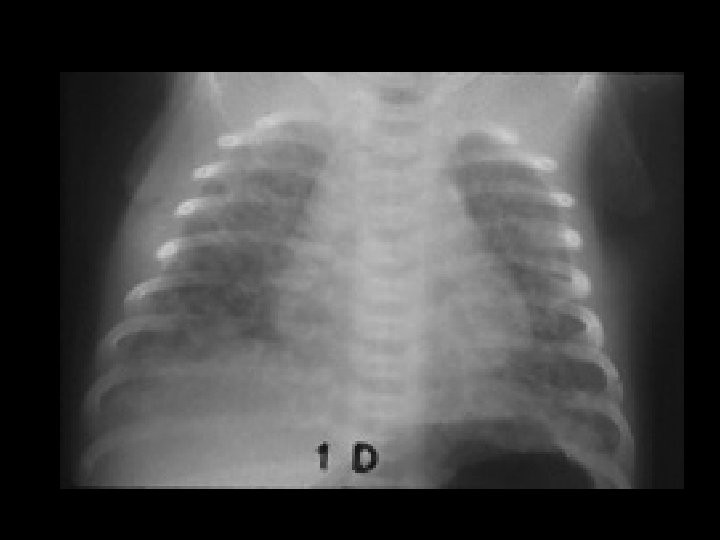

Neonatal Pneumonia • Findings: – diffuse bilateral granular opacities – normal lung volumes • Assoc/w PROM, mom (+) • Can lead to septicemia, shock, and death quickly • Classically Group B Strep • ddx: – TTN – HMD – meconium aspiration